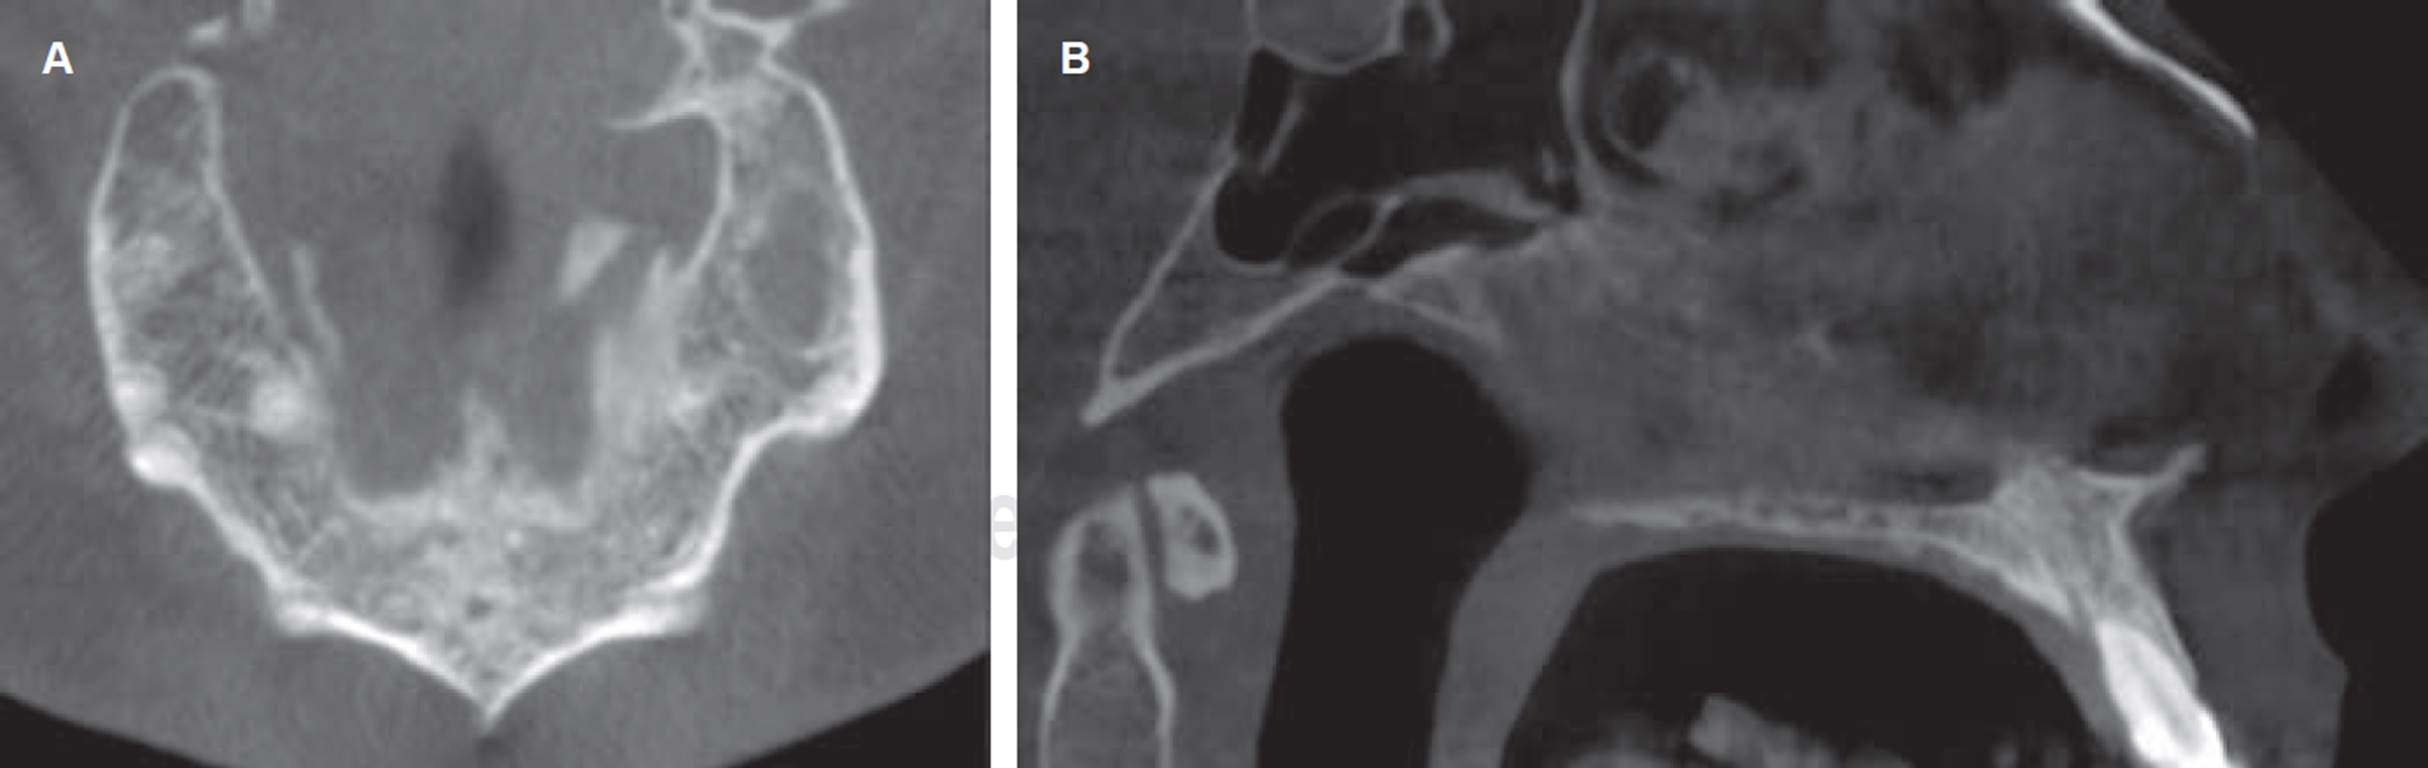

Se procedió a realizar una nueva intervención quirúrgica bajo anestesia local, donde se efectuó la enucleación y remoción quística con curetaje óseo con exodoncia de supernumerario. Finalmente se realiza relleno de cavidad con hueso microparticulado liofilizado xenogénico (Alpha Bio’s GRAFT) más una mem brana de colágeno reabsorbible (MEDPRIN ReDuraTM), suturando finalmente la mucosa comprometida (Figura 3A y B). La muestra obtenida (Figura 3C) fue enviada nuevamente a análisis histopatológico evidenciándose metaplasia de epitelio quístico escamoso no queratinizado, rodeado por una cápsula de tejido conjuntivo laxo con infiltrado inflamatorio crónico confirmando diagnóstico de quiste dentígero (Figura 3D). No se observaron recidivas tras seis meses de seguimiento de la lesión (Figura 4).

Figura 3 Enucleación de lesión quística. A) Se observa curetaje y remoción de pared quística en maxilar superior. B) Relleno de cavidad con hueso particulado xenogénico. C) Biopsia escisional, se observa muestra de tejido quístico. D) Estudio histopatológico de biopsia escisional teñida con hematoxilina-eosina, aumento 10x. Muestra de membrana quística con revestimiento epitelial escamoso no queratinizado, de pocas capas, y focos de calcificaciones distróficas, con infiltrado inflamatorio crónico en tejido conjuntivo.